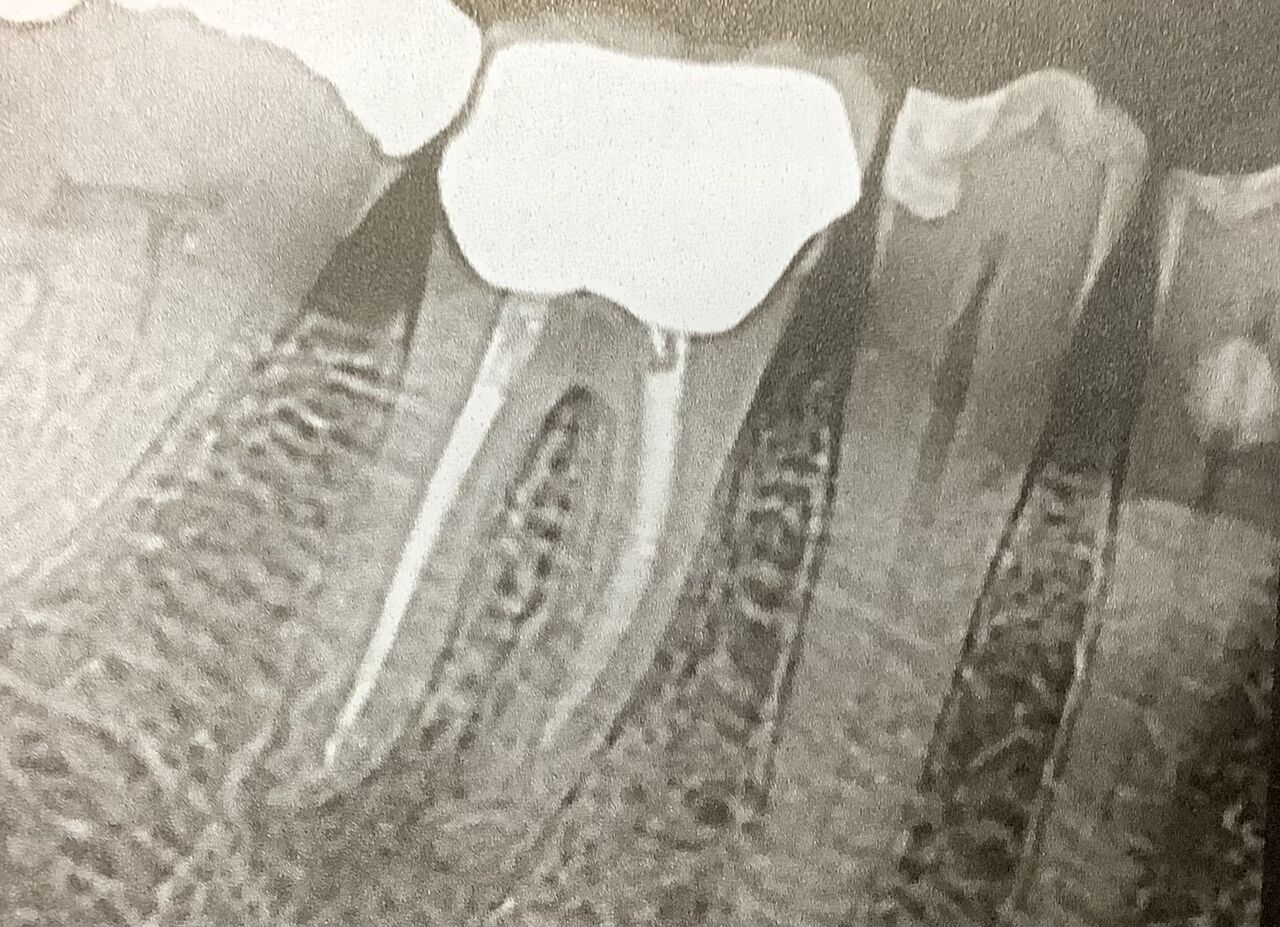

右下6番、根管治療をされた歯で、症状の有る根尖性歯周炎で垂直歯根破折を伴うもの。

前に根管治療を受けていて、痛みが有って、根っ子の先の炎症性病変で、しかも根っ子の方から縦にヒビが入っている。

レントゲン

様々ですが、このうちのどれかが見つかる。

⚪︎わずかに根っこに、あるいは上に方の骨の吸収、溶けてる。

⚪︎根っ子の横側、根っこに沿ってワキ側の歯根膜の黒いスジが広がっている。

⚪︎J型あるいは後光がさす、取り囲むような骨のカゲが有る。

分岐部、根っ子の分かれ目、マタにまで広がってるのが多い。

⚪︎根っ子がバラバラに見えることも。